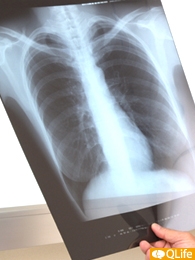

今年38歳になった息子が、毎年会社でおこなわれる検診で、胸のX線写真にカゲが写っているから精密検査を受けるようにと言われました。「カゲ」と聞いて不安になった息子はすぐに大きな病院を受診したのですが、詳しい検査の結果、肺がんであると診断されました。それも進行がんで、すでに骨にまで転移しているⅣ期の末期状態と言うのです。息子は独身なので、私たち両親が説明を一緒に聞いたのですが、「残り半年あるかどうか」と厳しい宣告を受けました。

親の立場として、子どもが助からない病気になるほど辛いことはないと思います。まして、息子さんはまだ30代とのこと。事実を受け止めるだけでも大変だと思います。ただ、肺がんが見つかったときにはすでに骨転移している末期状態だったからといって、前年に見落としがあったと断定するわけにはいきません。少なくとも、前年の検診結果(胸部X線写真)を取り寄せ、それを第三者の専門家に見てもらって明らかな異常があるかどうかを判断してもらう必要性が出てきます。また、そのような第三者の専門家の意見を聞くには、日本の現在のシステムでは弁護士を介する必要があるのです。そのためには、時間や費用も生じます。それに、いまの段階では、何よりも息子さん自身がそれを望むかどうかを確認することが求められます。

年に一度の検診や人間ドックを受けていれば、必ず病気は早期で発見されるはずという思いは、一般的に強いと思います。もちろん早期発見するために検診や人間ドックがあるわけですが、なかにはかなり急速に進行するがんもあると聞いています。この方の息子さんがどうだったのかはわかりませんが、毎年検診を受けていて、かなり進んだ病気が見つかった場合、前年までの結果も含めて見解を伝えることが必要ではないかと思います。